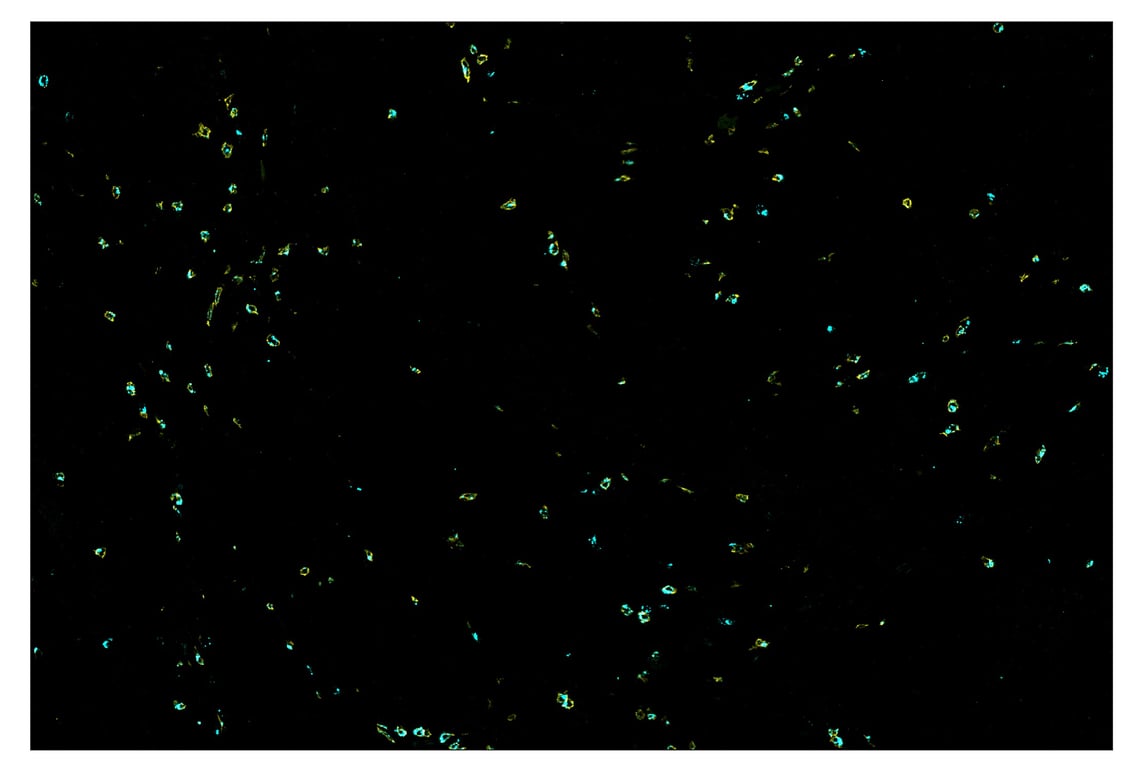

SignalStar™ multiplex immunohistochemical analysis of paraffin-embedded human infiltrating ductal carcinoma of the breast using CD8α (D8A8Y) & CO-0004-750 SignalStar™ Oligo-Antibody Pair #62750 (cyan) and HER2/ErbB2 (D8F12) & CO-0019-488 SignalStar™ Oligo-Antibody Pair #31149 (green). All fluorophores have been assigned a pseudocolor, as indicated.

Immunohistochemistry Image 1: CD8 alpha (D8A8Y) & CO-0004-594 SignalStar<sup>™</sup> Oligo-Antibody Pair